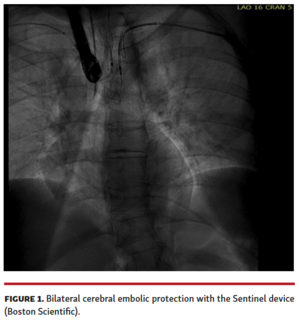

Alfonso Jurado-Román, MD, PhD; Artemio Garcia, MD; Raúl Moreno-Gómez, MD, PhD

A 61-year-old patient presented an acute occlusion of the mid-right coronary artery.